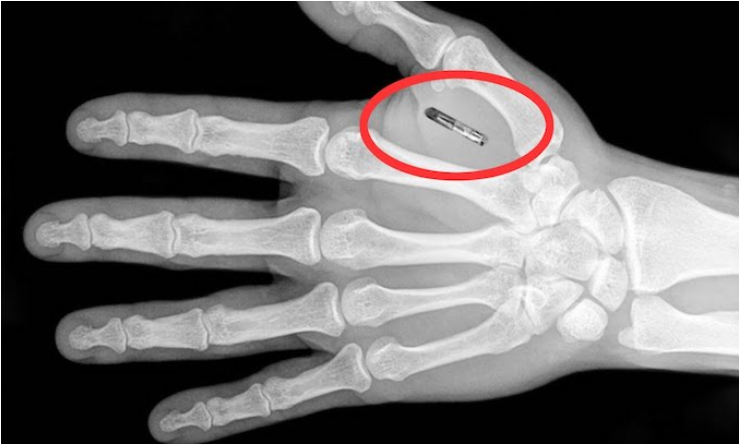

Le docteur Carl W. Sanders(Né le 6 Février 1935-Mort à 80 ans le 3 Janvier, 2016), qui a participé au développement de la puce RFID, est un ingénieur en électronique et un inventeur qui a travaillé auprès de nombreuses organisations gouvernementales et de compagnies telles que IBM, General Electric, Honeywell et Teledyn. Durant 32 ans, il a œuvré dans le domaine bio médical.

En 1968, le docteur Sanders participe à un projet de recherche concernant un pontage spinal, afin de soigner une dame dont l’épine dorsale était endommagée. Le but était de trouver une solution pour relier les nerfs moteurs. Ce projet aboutit à la création d’une micro-puce (microchip) qui se recharge de façon autonome grâce aux changements de température du corps humain, ce qui lui donne une durée de vie pratiquement illimitée.

rfid15 Pour ce faire, elle possède un circuit de rechargement thermo électrique, ainsi qu’une petite pile au lithium rechargeable. Il fut confirmé au Dr. Sanders par un docteur du Centre Médical de Boston que si la micro puce venait à se briser dans le corps humain, en raison du lithium, cela provoquerait une grave plaie, douloureuse et remplie de pus. Mais ″on″ décida malgré cela d’utiliser une pile au lithium pour la micropuce…

On découvrit ensuite que les 2 endroits du corps humain où la température change le plus rapidement sont le front (juste en bas de la naissance des cheveux) et le revers de la main. Par suite de considérations financières (la puce ne ″rapportait pas assez″), il fut signifié aux responsables du projet qu’ils devaient trouver de nouvelles applications pour cette puce.

Comme il avait été remarqué que le changement de fréquence de la micro-puce avait des effets sur le comportement une fois implantée dans le corps, ″on″ orienta les recherches sur la possibilité de modifier le comportement humain à l’aide de la micro-puce. Cette dernière pouvait diffuser un signal qui stimulait certaines parties du cerveau. On pouvait, par exemple, augmenter le taux d’adrénaline, ce qui provoquait un changement de comportement…De plus, selon les découvertes effectuées par Carl Sanders et son équipe, le contrôle des naissances peut-être effectué via l’utilisation de la puce qui arrête le rendement de la glande pituitaire (hypophyse), ce qui produit une ménopause instantanée. Ceci a été examiné en Inde et dans d’autres parties du monde.